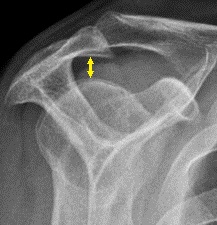

- 어깨 X선에서 정상적인 봉우리밑공간은 9mm~10mm 정도로, 남성에서 훨씬 크며 나이가 들수록 조금씩 크기가 줄어든다.[2] 중년기에 봉우리밑공간의 크기가 6mm보다 작다면 병적인 상태로 보며, 위가시근 힘줄의 파열을 시사하는 소견일 수 있다.[2]

- 어깨 X선에서 정상적인 봉우리밑공간(subacromial space)은 9–10mm 정도로, 남성에서 훨씬 크며 나이가 들수록 조금씩 크기가 줄어든다.[2] 중년기에 봉우리밑공간의 크기가 6mm보다 작다면 병적 상태로 보며, 위가시근 힘줄의 파열을 시사하는 소견일 수 있다.[2]